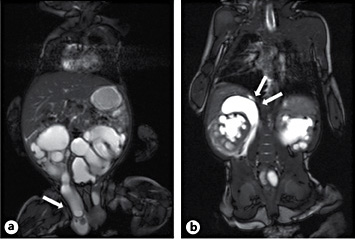

At the age of 10 weeks, surgical repair for bilateral inguinal hernia was planned within 1 month. While his baseline serum creatinine was 40 µmol/l (0.45 mg/dl), there was a sudden rise to 69 µmol/l (0.78 mg/dl). The boy showed mild discomfort, the abdomen was non-tender, the inguinal hernias appeared unchanged and were not painful. Dehydration and UTI were ruled out. Renal ultrasound showed the formally known dilation on the left side, yet hydroureteronephrosis on the right side had increased significantly. On this side, a novel fluid collection surrounding the upper pole was noted, which prompted an MRI study (fig. 1). This revealed ureteroinguinal herniation of the right megaureter. A fluid collection around the right upper pole raised suspicion of a kidney blow out. Surgical exploration was conducted on the same day.